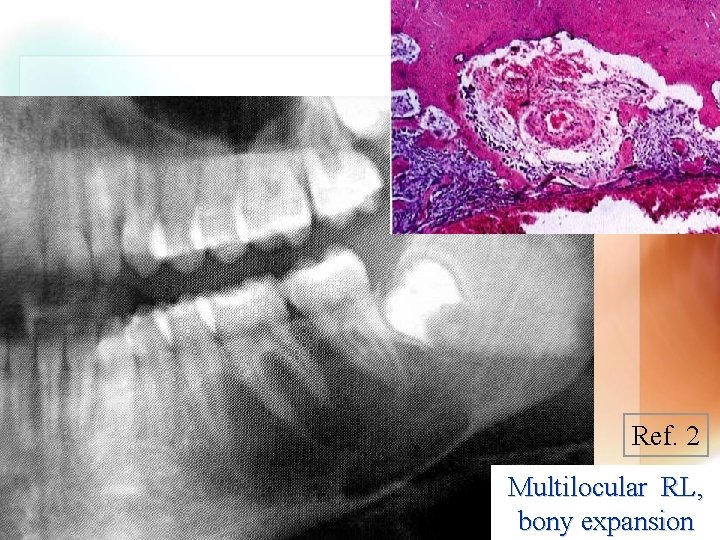

Aneurysmal bone cyst Unilocular RL Ref. 2 Multilocular RL, bony expansion Ref. 2 Ref. 1 | | | 90% < 30 y/o; Md. > Max. Proliferative response of vascular tissue R-L, expansile osteolytic process Wen. Chen Wang